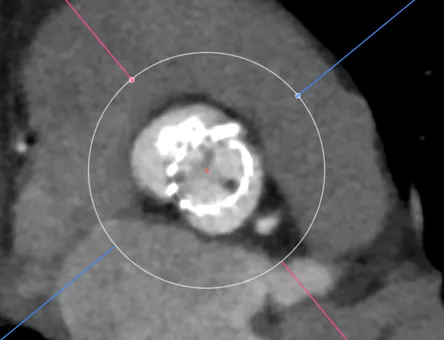

比如病例-6.可以看到瓣架比瓣环小了很多,这个时候虚拟瓣环是没有任何封堵作用的。

这个病例是一个明显的type0型二叶瓣挤压瓣膜,锚定区和封堵区都在瓣上,瓣上挤压瓣膜成椭圆导致瓣环位置跟着变椭圆。这时候如果想要没有瓣周漏,就一定要高放让封堵贴合瓣上限制的区域。Oversize是贴不到的。

再一个例子,病例-7,这个更明显了,可以看到虚拟的地方有一半的空隙。